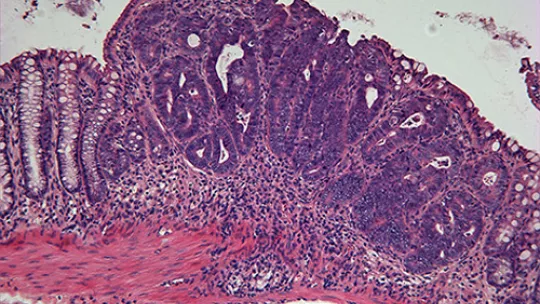

Un equipo liderado por Angel Rodríguez Nebreda del Instituto de Investigación Biomédica (IRB Barcelona) identifica una función dual de la proteína p38 MAPK en cáncer de colon. El trabajo demuestra, por un lado, que p38 es importante para mantener en buen estado la barrera epitelial que protege al intestino frente a agentes tóxicos, lo que contribuye a que se formen menos tumores. Por otro lado y curiosamente, cuando ya se ha formado un tumor, p38 es necesaria para la supervivencia y proliferación de las células tumorales de colon facilitando el desarrollo del tumor.

Un importante hallazgo del presente estudio está relacionado con la función que desempeña p38 manteniendo intacta la estructura de la barrera epitelial, que protege al intestino frente a agentes tóxicos o patógenos. Los ratones a los que se había eliminado genéticamente p38 de las células epiteliales que forman la barrera intestinal, y se les aplicaba un protocolo cancerígeno que causa mutaciones e inflamación, desarrollaron el doble de tumores que aquellos ratones que, tratados con el mismo protocolo cancerígeno, tenían p38.